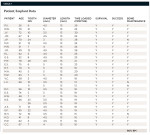

This study consisted of 27 consecutively treated patients who received 29 implants (Table 1). The age of the patients ranged from 26 to 85 years. All patients required extraction of one or more anterior teeth in the first bicuspid or mesial portion of the dentition in either the maxillary or mandibular arch. All patients were presented with alternative treatment options and signed informed consent forms explaining risks associated with implant therapy. Because no deviation from standard treatment rendered in a periodontal specialty practice existed, and the study did not involve any unapproved or special materials unique to the study, no special considerations regarding informed consent were necessary.

The data concerning implant site distribution, fixture dimensions, type of bone augmentation, and time loaded with the final restoration is found in Table 1.